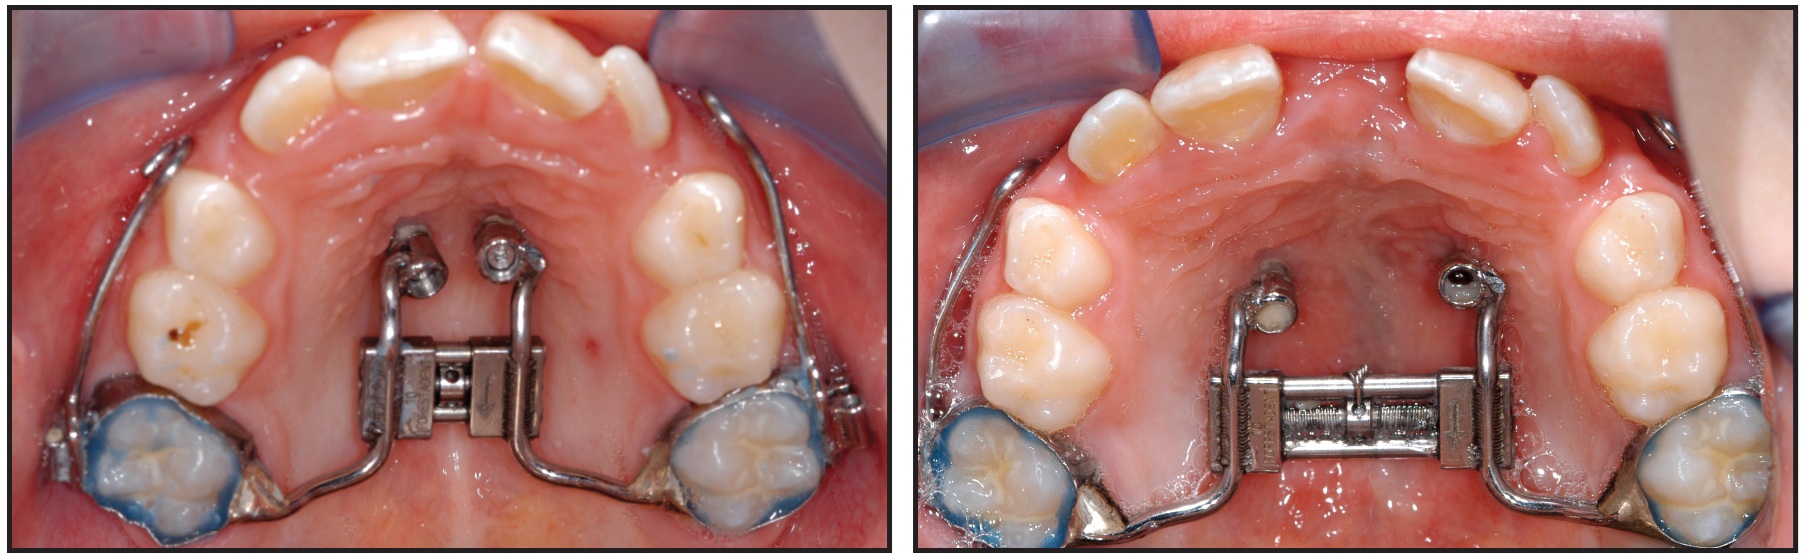

Fig. 9 Alignment of impacted maxillary left central and lateral incisors with anchorage from bracket abutment on 2mm x 11mm Benefit mini-implant. Additional bracket was welded to bracket abutment to allow ligation of two segmental .016" x .022" TMA wires.